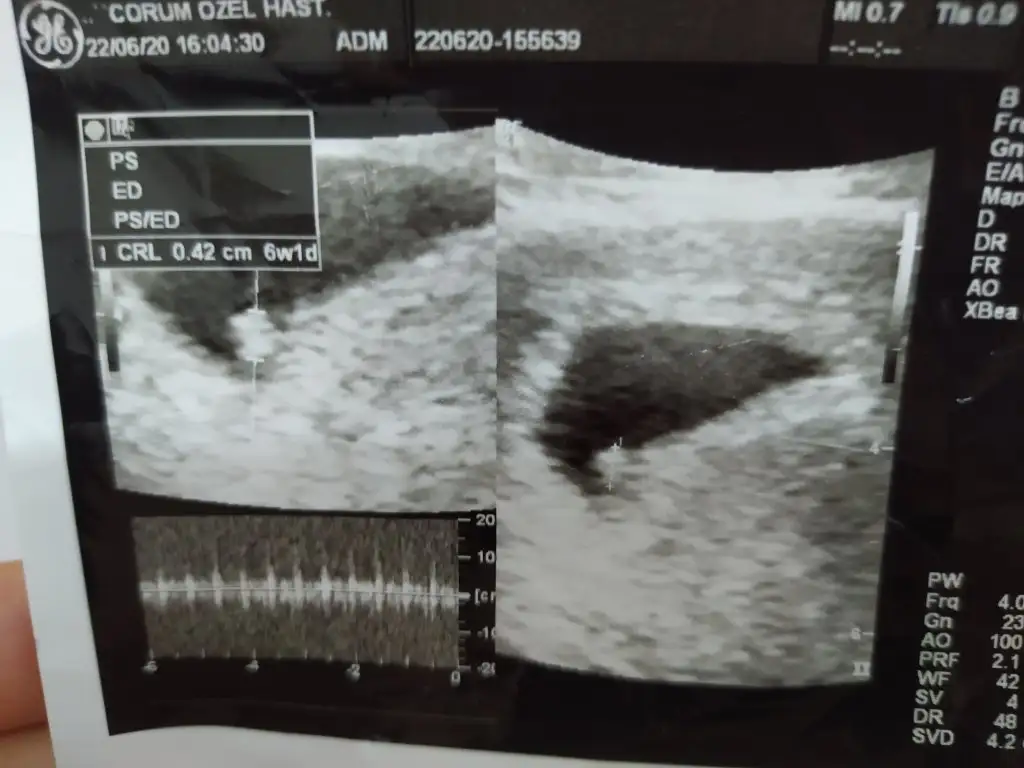

Merhaba 12+6 bugün 2 li test için çekilen ultrason resimlerinden cinsiyet tahmini yapabilen olurmu

Eklentiler

• IMG_20200814_125749.webp

IMG_20200814_125749.webp

17,9 KB · Görüntüleme: 66

• IMG_20200814_115015.webp

IMG_20200814_115015.webp

21,5 KB · Görüntüleme: 62

• IMG_20200814_115009.webp

IMG_20200814_115009.webp

23,4 KB · Görüntüleme: 67